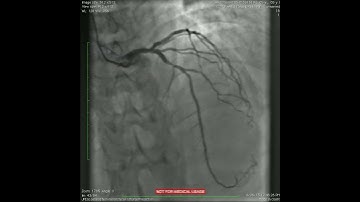

Transradial approach, from complex PCI to peripheral intervention